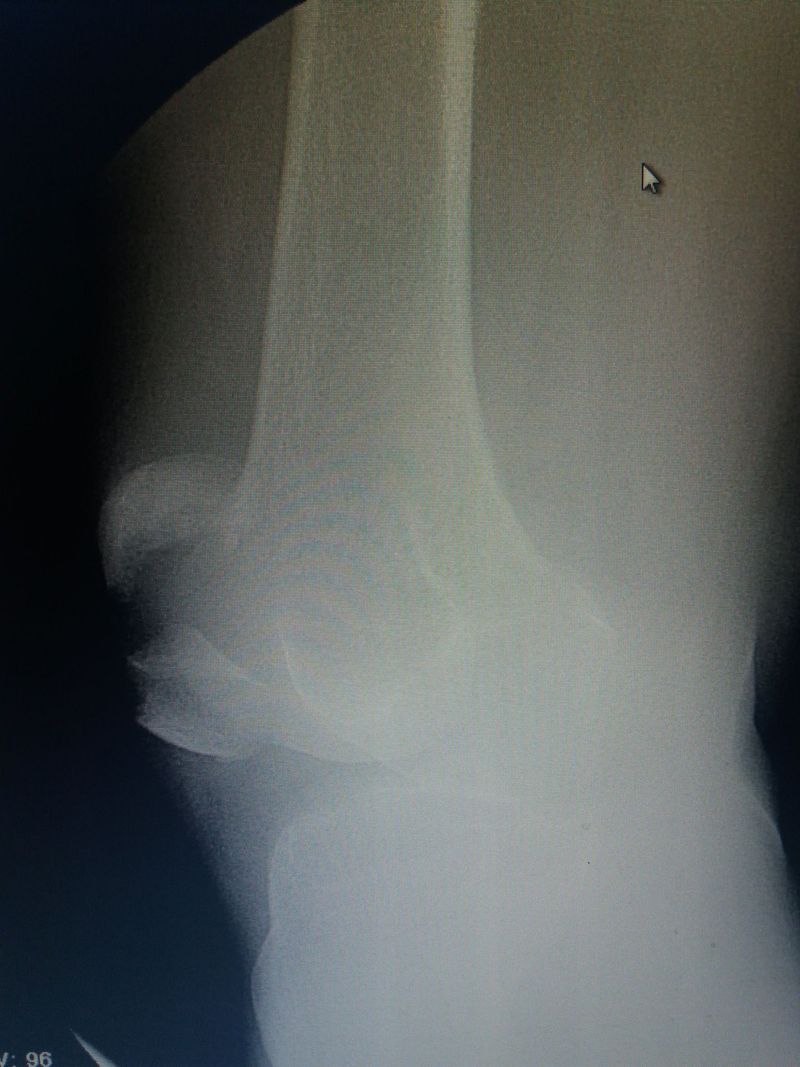

Fracture of patella

Yes, transverse fracture of Patella, k-wire in a Figure 8 under imaging would do. Great bone density, young patient ?

No patient 57 year old !